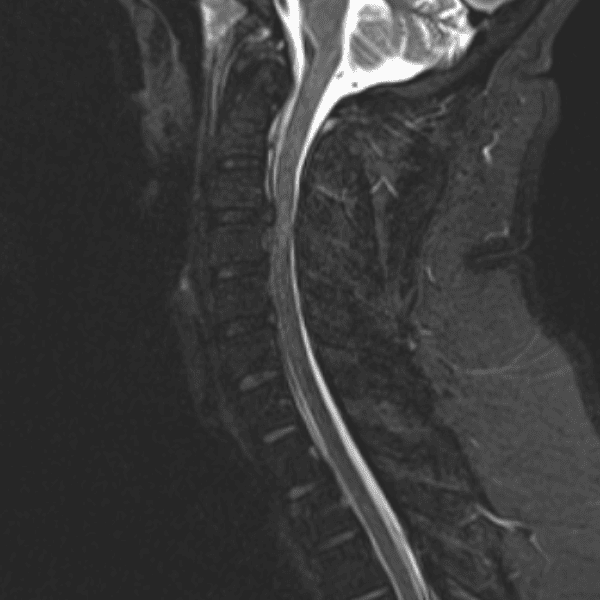

Simulates call by including subtle or difficult cases and some normals.

35 cases